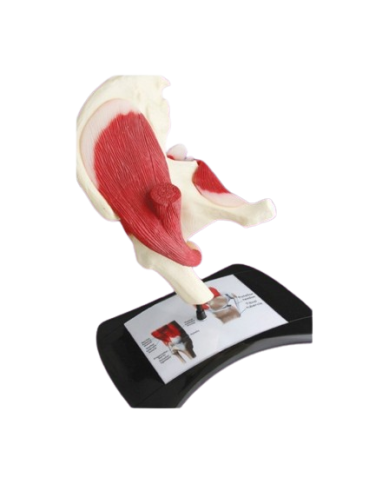

Modello anatomico PER FORNITURE CASE FARMACEUTICHE

Modello anatomico PER FORNITURE CASE FARMACEUTICHE

Modello anatomico PER FORNITURE CASE FARMACEUTICHE

Modello anatomico PER FORNITURE CASE FARMACEUTICHE

Modello anatomico PER FORNITURE CASE FARMACEUTICHE

Modello anatomico PER FORNITURE CASE FARMACEUTICHE

Modello anatomico PER FORNITURE CASE FARMACEUTICHE

Modello anatomico PER FORNITURE CASE FARMACEUTICHE

Modello anatomico PER FORNITURE CASE FARMACEUTICHE

Modello anatomico PER FORNITURE CASE FARMACEUTICHE

Modello anatomico PER FORNITURE CASE FARMACEUTICHE

Modello anatomico PER FORNITURE CASE FARMACEUTICHE

Modello anatomico PER FORNITURE CASE FARMACEUTICHE

Modello anatomico PER FORNITURE CASE FARMACEUTICHE

Modello anatomico PER FORNITURE CASE FARMACEUTICHE

Modello anatomico PER FORNITURE CASE FARMACEUTICHE

Modello anatomico PER FORNITURE CASE FARMACEUTICHE

Modello anatomico PER FORNITURE CASE FARMACEUTICHE

Modello anatomico PER FORNITURE CASE FARMACEUTICHE

Modello anatomico PER FORNITURE CASE FARMACEUTICHE

Modello anatomico PER FORNITURE CASE FARMACEUTICHE

Modello anatomico PER FORNITURE CASE FARMACEUTICHE